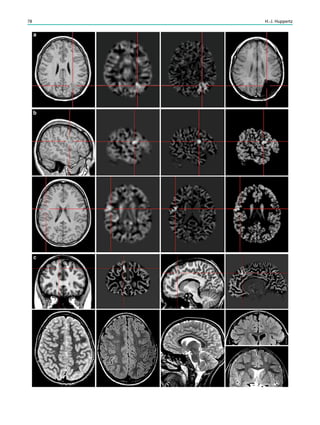

Contents

1 Introduction.......................................................................... 29

2 Theoretical Considerations................................................. 29

3 Clinical Practice................................................................... 30

4 Requirements for MR Quality........................................... 32

4.1 Orientation ............................................................................. 32